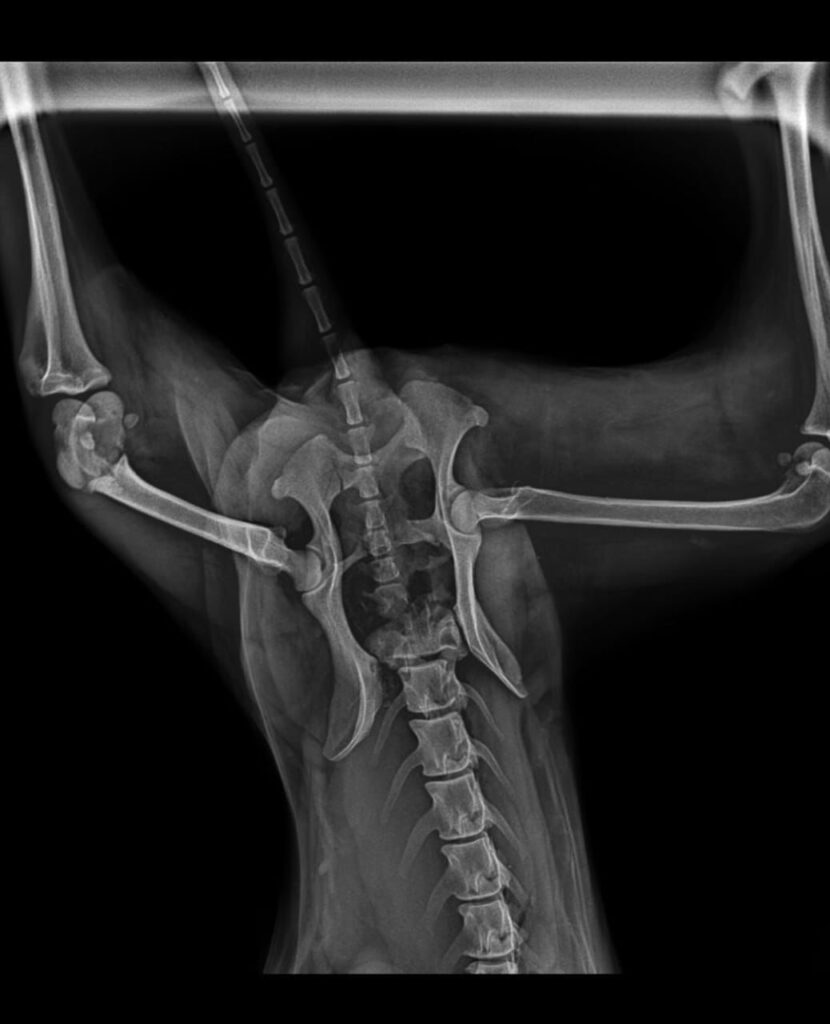

Cinco fracturas y una cirugía clave para su recuperación

El impacto le provocó cinco fracturas, lo que hoy le genera grandes dificultades para moverse.

Desde ese momento, su familia inició una carrera contrarreloj para ayudarla a recuperarse. Hasta ahora se hicieron cargo de consultas veterinarias, radiografías, medicamentos y distintos tratamientos necesarios para estabilizarla.